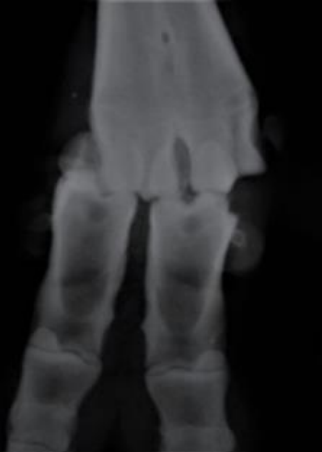

Analise a imagem a seguir.

Na exposição radiográfica dorsopalmar da extremidade distal de um bovino, qual é a alteração observada?